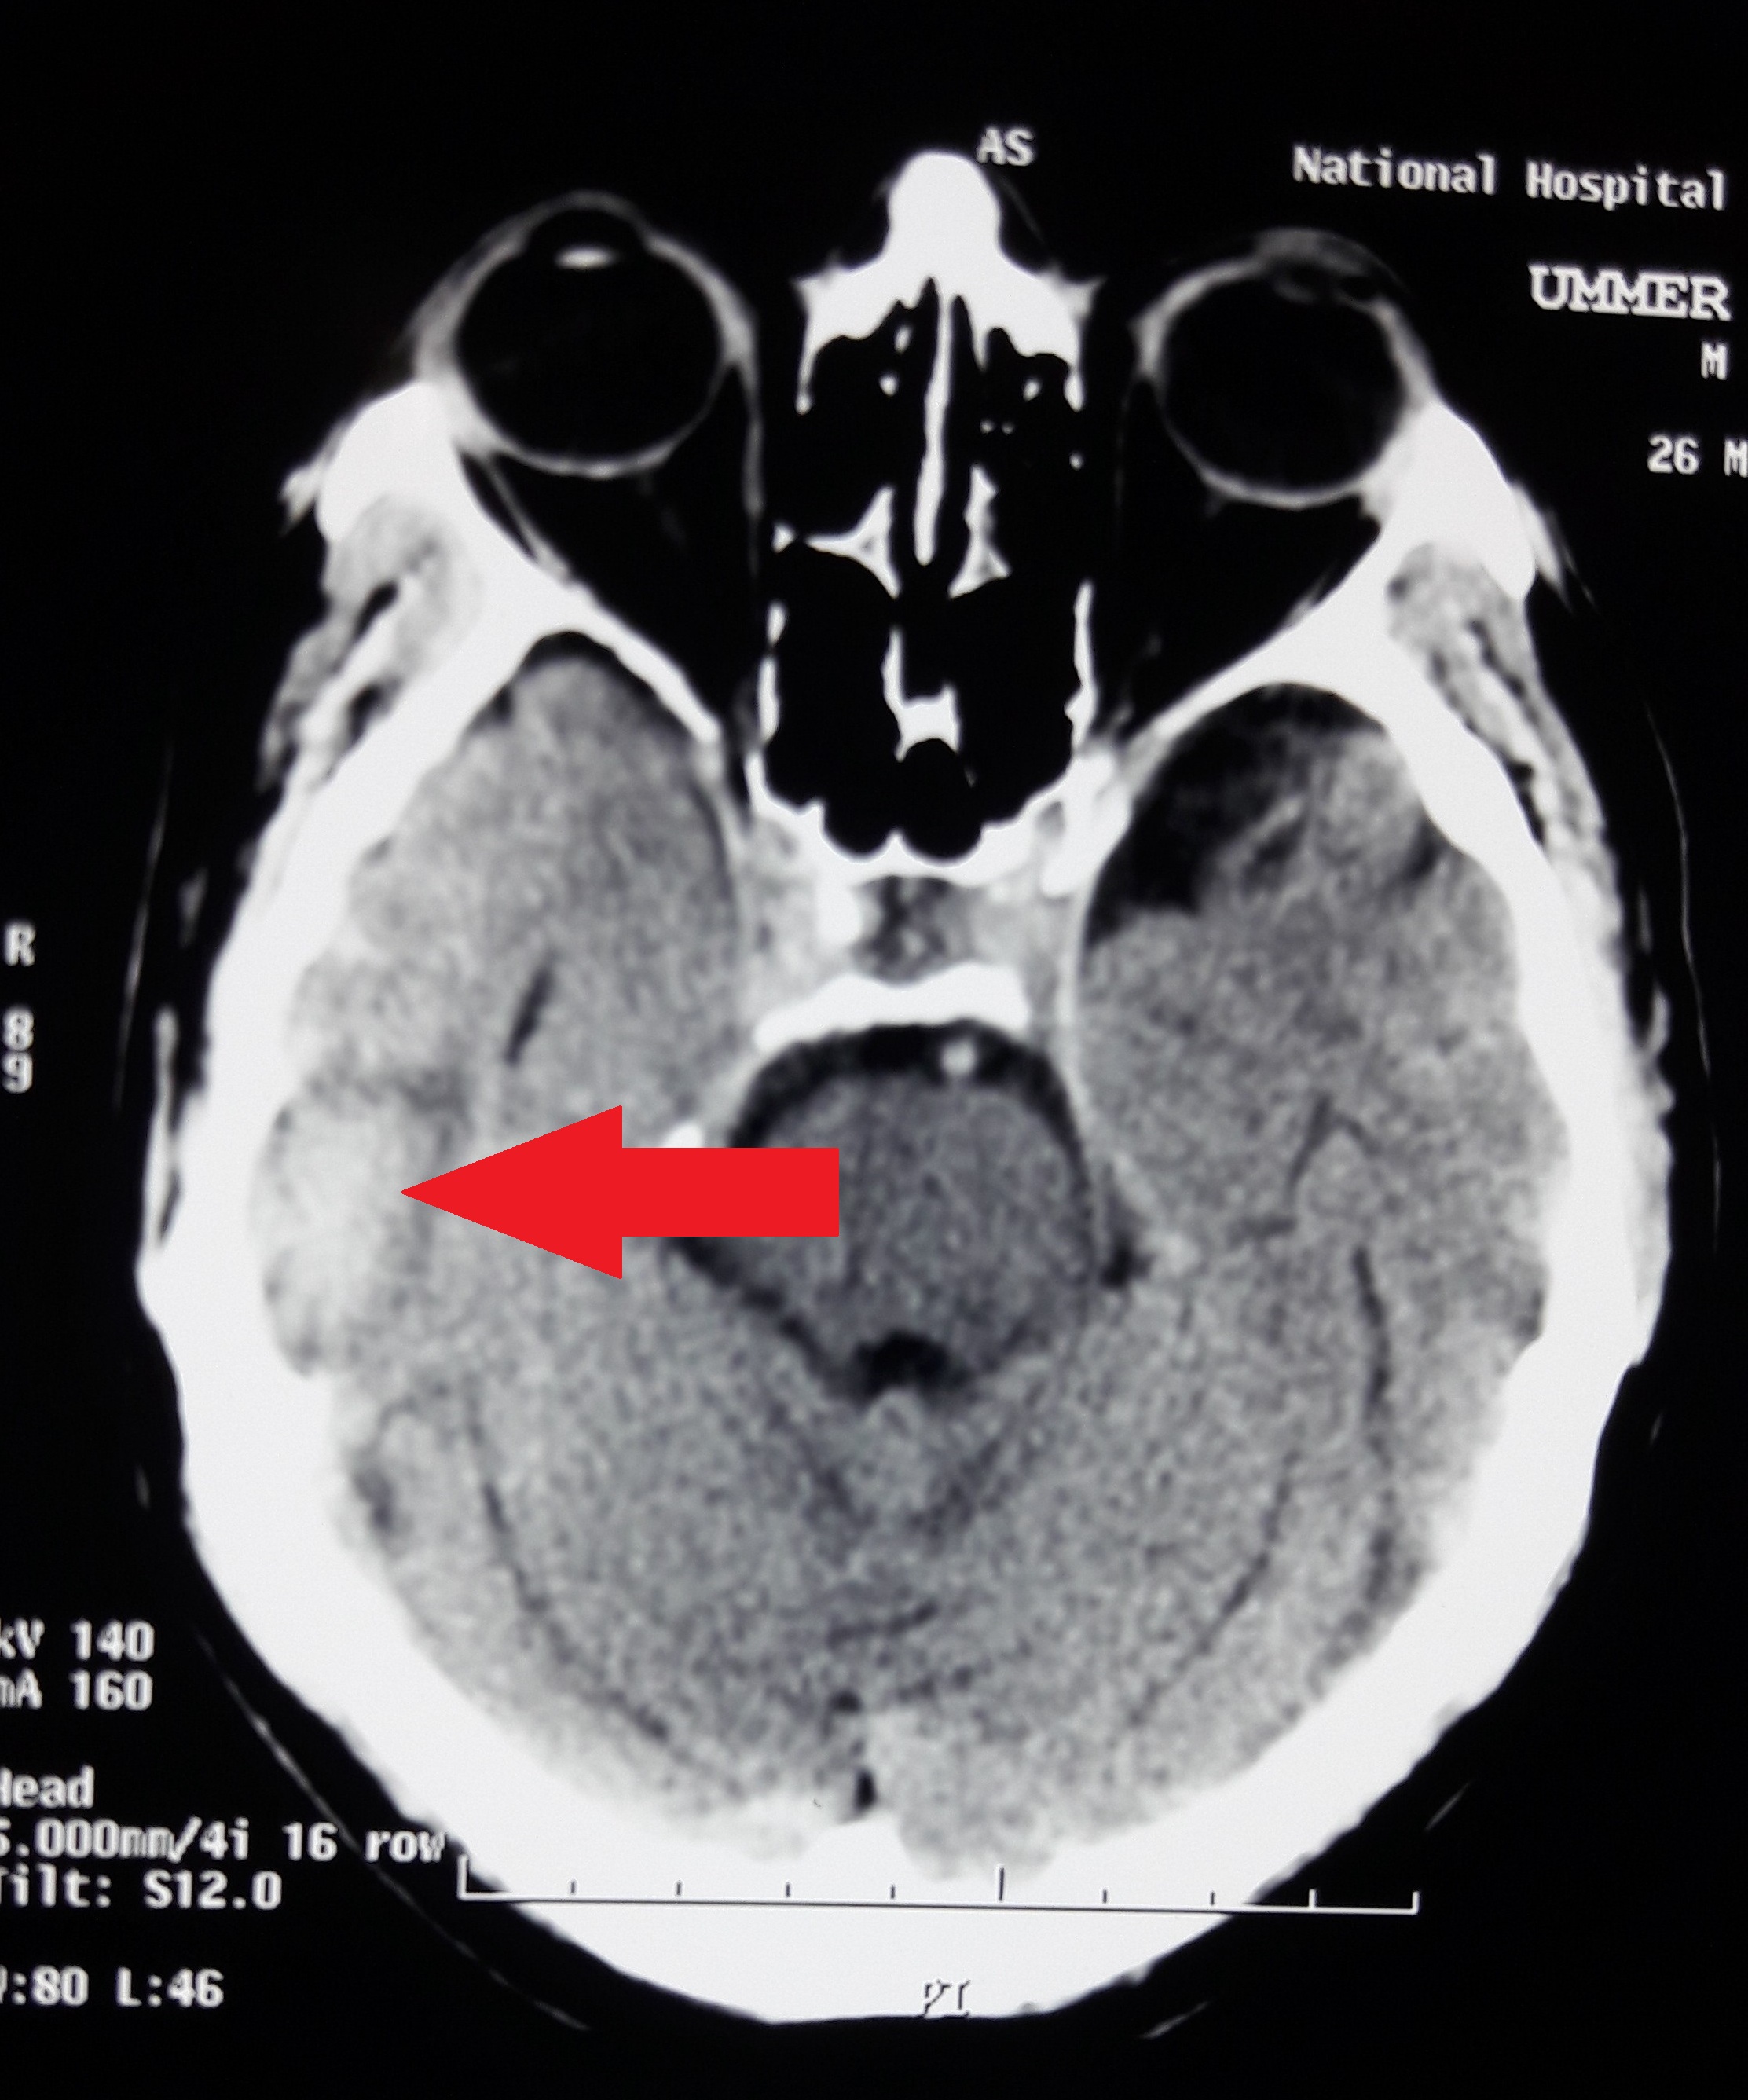

Nonketotic hyperglycemia: The culprit behind refractory seizures in a case of traumatic brain injury

Hyperglycemia, seizures, temporal lobe epilepsy, traumatic brain injuryAbstract